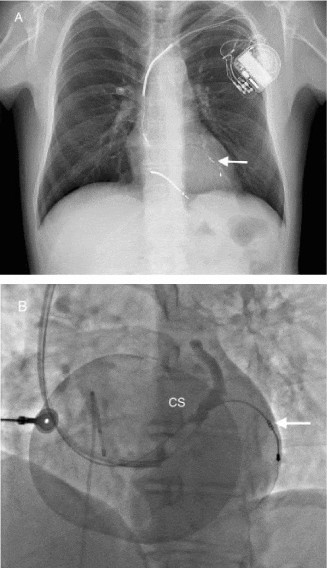

A 49-year-old male was admitted to our hospital in October 2015 to perform a lead extraction procedure for a CRT device-related infection. In 2008, after evidence of dilated cardiomyopathy he received a CRT defibrillator employing three different leads among which an Attain StarFix™ Model 4195 (Medtronic Inc., Minneapolis, MN, USA) was implanted; this is an unipolar lead with an extendable active fixation mechanism through small polyurethane lobes which, after deployment, are conceived to firmly fixate the lead into a CS venous collateral. The patient had a good clinical response to the CRT therapy but after 5 years he had a reintervention to fix a traumatic fracture of the StarFix™ lead; after 14 months signs of local pocket infection appeared without signs or symptoms of systemic infection (white cells 7660/uL, ESR 12 mm/hr, procalcytonin 0,10 ng/ml). Hospital admission was performed to extract the entire CRT system. The generator was removed and transvenous extraction of the leads was attempted. Two of the three leads were completely removed with conventional mechanical dilatation [4], however, multiple attempts to remove the StarFix™ lead were unsuccessful since it appeared to be entrapped into a CS side-branch most likely occluded by thrombosis (Figure 1). Therefore surgical extraction of the lead was considered indicated.

Figure 1:

The procedure was performed through a standard median sternotomy; an intraoperative trans-esophageal echocardiogram showed a 30% ejection fraction with moderate mitral regurgitation. Due to the hemodynamic instability during cardiac manipulation it was decided to perform lead extraction on pump with a beating heart. The ascending aorta and the right atrium were cannulated and normothermic cardiopulmonary bypass instituted. The heart was then lifted upwards and on the right side exposing the distal part of the lead which was entrapped into the posterior left ventricular coronary vein. To facilitate lead extraction an Octopus Tissue Stabilizer® (Medtronic Inc., Minneapolis, MN, USA) was used for focal immobilization of the ventricular wall; a 4 cm incision of the vein confirmed vein thrombosis and exposed the lead which was isolated and could be removed only after dissection of the fixing polyurethane lobes which were incorporated in the vein wall (Figure 2). A new bipolar drug-eluting MyoDex 1084T epicardial lead (St. Jude Medical, Saint Paul, MN, USA) was screwed in the lateral wall of the left ventricle and tunnelled in the right prepectoral region for the connection to a new CRT device. The patient was weaned from bypass without difficulty and the post-operative course was uneventful.

Figure 2: